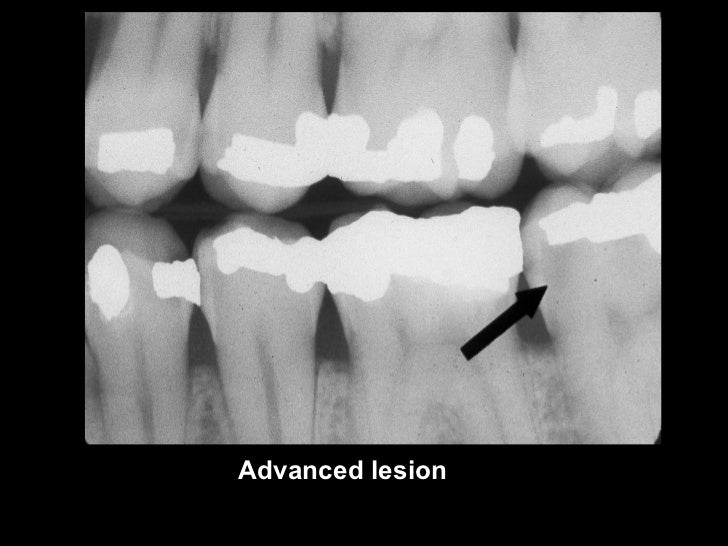

radiographiccariesdiagnosis